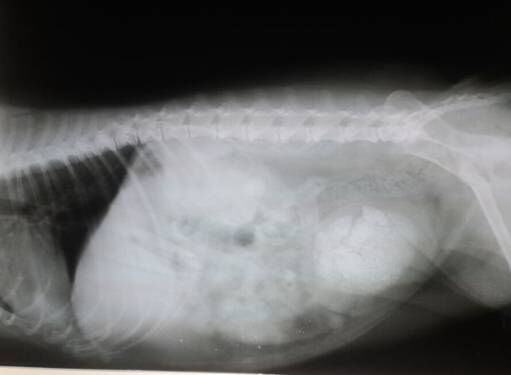

X光片,一个病例中膀胱内结石。

根据结石发生的部位不同,采取的手术方案也不尽相同。可以很快解除临床上出现的症状,手术治疗因为不能从根本上解决结石发生的原因,不能降低结石复发的概率。图中所示的两张X光片中,为两个单独的病例,结石的位置都位于膀胱内。同时也需要无菌逆向从尿道口插入导尿管来确定尿道是否有结石,正向、逆向将结石冲洗干净。有相关资料报道,母犬结石80%为磷酸铵镁,该种结石的产生通常伴随有泌尿道的感染,尤其是一些产尿素酶的细菌如葡萄球菌、变形杆菌等,尿液PH值一般中性偏碱。因此膀胱结石取出后术后同时需要抗菌。对于结石出现在尿道的病例,如果结石大小必须比尿道最窄处的直径小且表面光滑的结石通过尿道冲洗,可能会把结石冲洗出来。但若不能通过该种方法将结石取出来的病例,会需要借助一些特殊的造影方法,来确定结石的位置,进行尿道造口。具体采用哪种手术方案,要根据实际病例及结石的性质和结石在泌尿道的位置来确定。